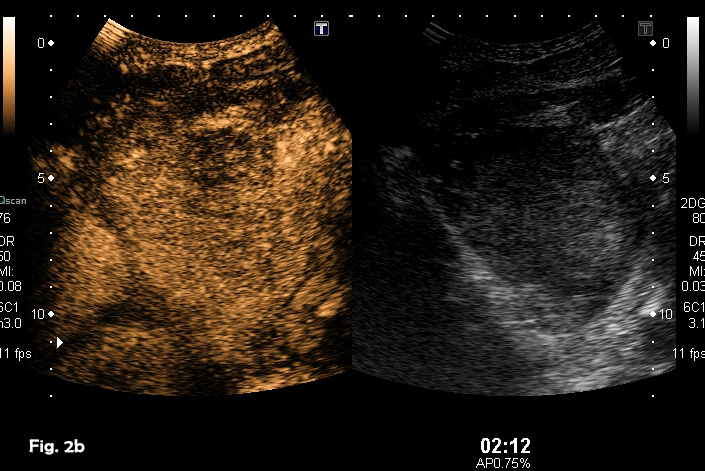

A previously healthy 39-year-old male was referred because of a hepatic mass, found incidentally He was a professional sportsman and regularly participated in competitions. He had taken anabolic steroids for 6-8 weeks two or three times per year from 24 – 32 years old approximately. The remainder of the medical history was unremarkable. Laboratory results showed a slight elevation of ALT and AST with normal bilirubin and alpha-fetoprotein levels. Physical examination was otherwise normal. An abdominal ultrasound showed a well-defined 8.5 x 7.7 cm heterogeneous mass with a hypoechoic peripheral halo in the left lobe of the liver, segments 2 and 3 (Fig 1). A small nodule-in-nodule appearance was evident within the mass as well as some vascularity on colour Doppler. Following the administration of an ultrasound contrast agent (SonoVueTM), the mass showed homogeneous hyper-enhancement in the arterial phase (Fig 2a) (video 1), with wash-out in the late phase in only part of the lesion (video 2), specifically, the nodule-in-nodule appearance area (Fig 2b). These appearances were suggestive of a hepatocellular adenoma with areas of malignant transformation and this was confirmed by both ultrasound guided fine-needle aspiration cytology (video 3) and subsequent histological examination of the surgically resected tumour.

![Hepatic adenoma with focal hepatocellular carcinoma</br> [Aug 2016]](http://s834315022.websitehome.co.uk/wp-content/uploads/2020/11/cotm_august2016_fig01.jpg)